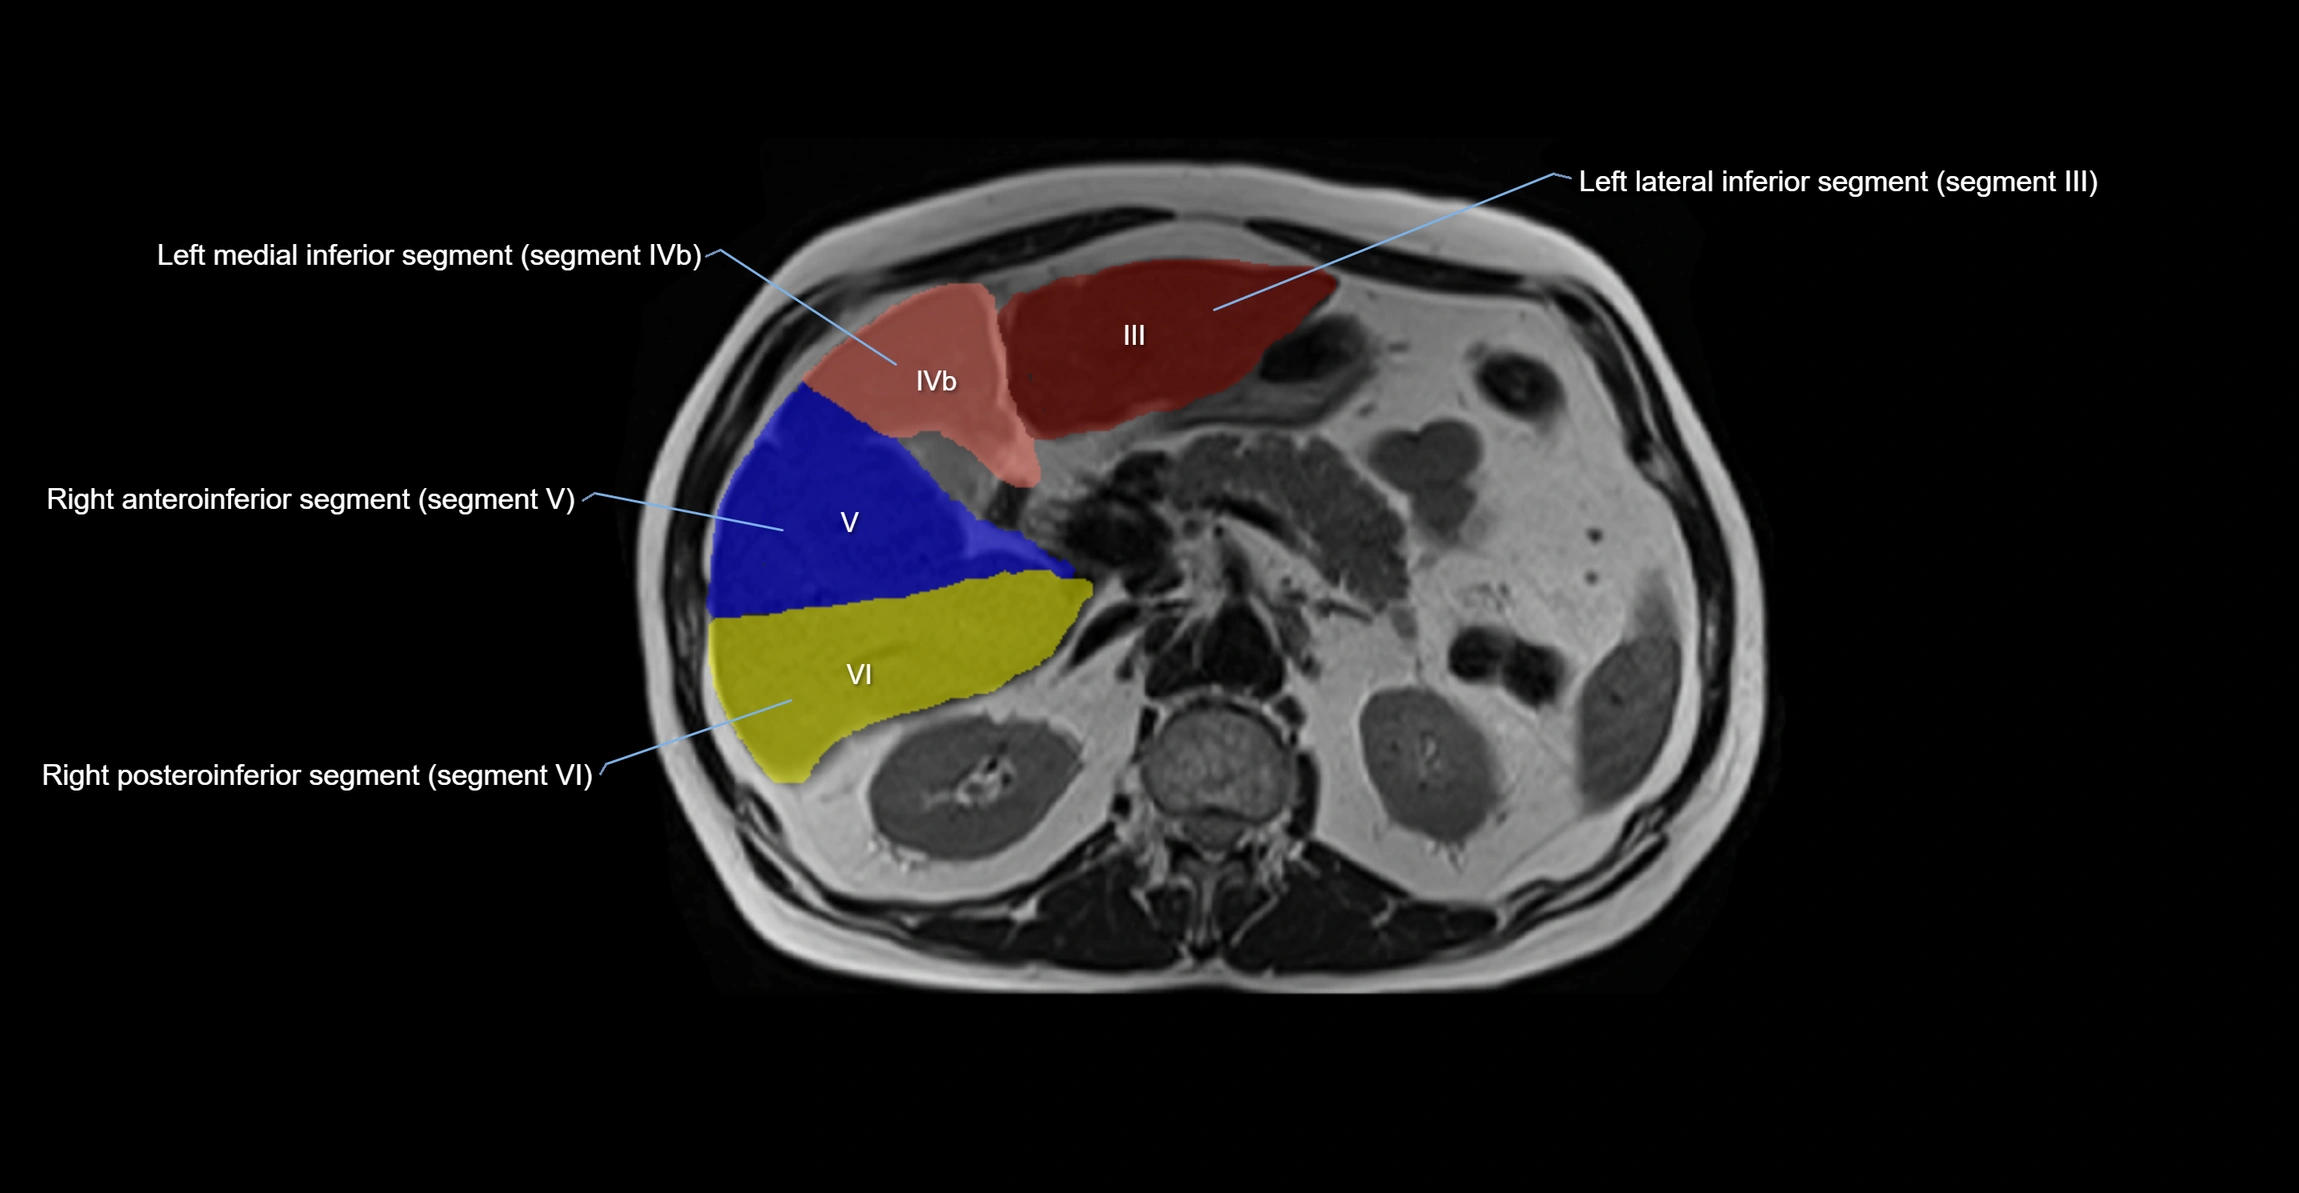

The caudate lobe of the liver is a distinct anatomical subdivision of the liver, designated as segment I in Couinaud’s classification. It lies on the posterior surface of the liver, between the fissure for the ligamentum venosum (left boundary) and the groove for the inferior vena cava (IVC) (right boundary). Superiorly, it is related to the posterior liver surface, and inferiorly it is separated from the left lobe by the porta hepatis.

• Segment I (Couinaud classification)